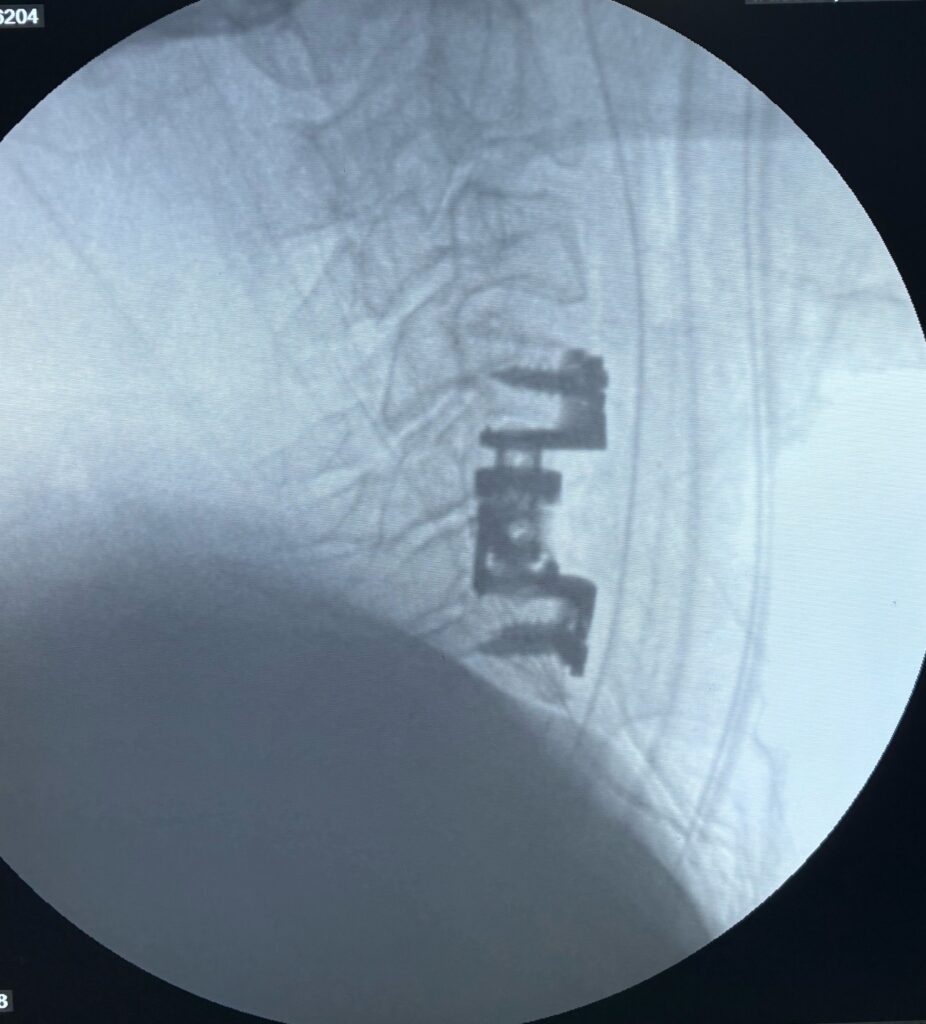

Common surgical procedures include:

- Spinal fixation: To stabilize fractured bones

- Decompression surgery: To relieve nerve pressure

Modern spine surgery uses advanced techniques that improve safety and recovery time.

Cases treated by Spine Specialist Dr. Gaurav Sandeep Gupta